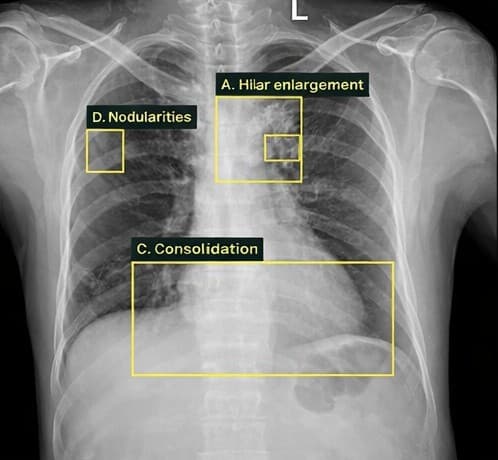

Lung tumor

Tuberculosis

TB | 0.94Sputum collection pending

Tuberculosis | 0.94Sputum collection pending